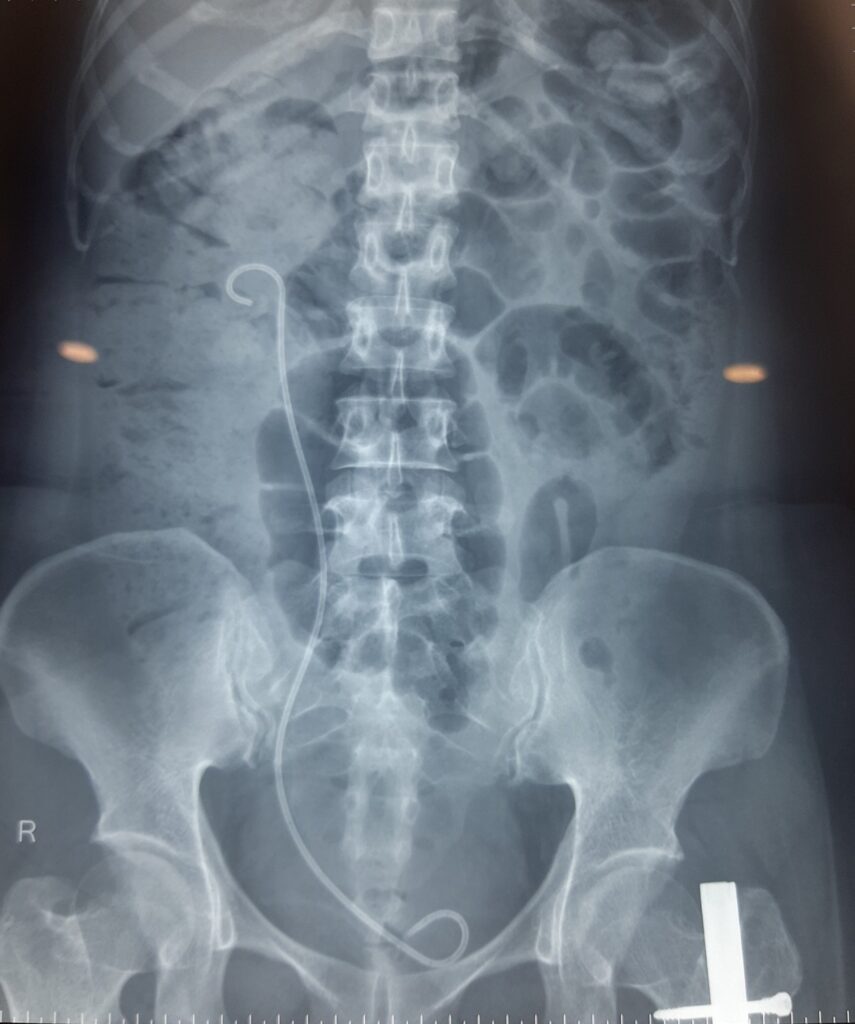

Trong vòng 3 giờ đồng hồ, đội ngũ y bác sĩ của bệnh viện với nhiều kinh nghiệm trong xử trí các trường hợp sỏi phức tạp đã thực hiện thành công ca phẫu thuật, loại bỏ sỏi khỏi đường tiết niệu cũng như đặt sonde JJ mới. Sau phẫu thuật, tình trạng sức khỏe của chị T. ổn định, diễn tiến tốt và đã được xuất viện sau 5 ngày điều trị. Chụp phim X quang kiểm tra sau mổ cho thấy chị T. đã hết sỏi trong thận.

Hình ảnh X quang kiểm tra sau phẫu thuật, sỏi đường tiết niệu đã được loại bỏ hoàn toàn, sonde JJ mới được đặt cho người bệnh